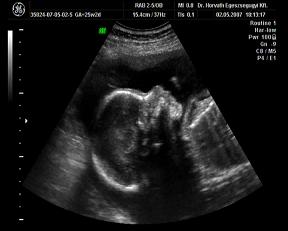

Néhány kép, nagyon kis drága volt, szépen mutatta magát:

egy 2D-s profil

És néhány 3D-s:

Kép Kép Kép Kép

Hát ilyenek vagyunk a 25. héten.:D